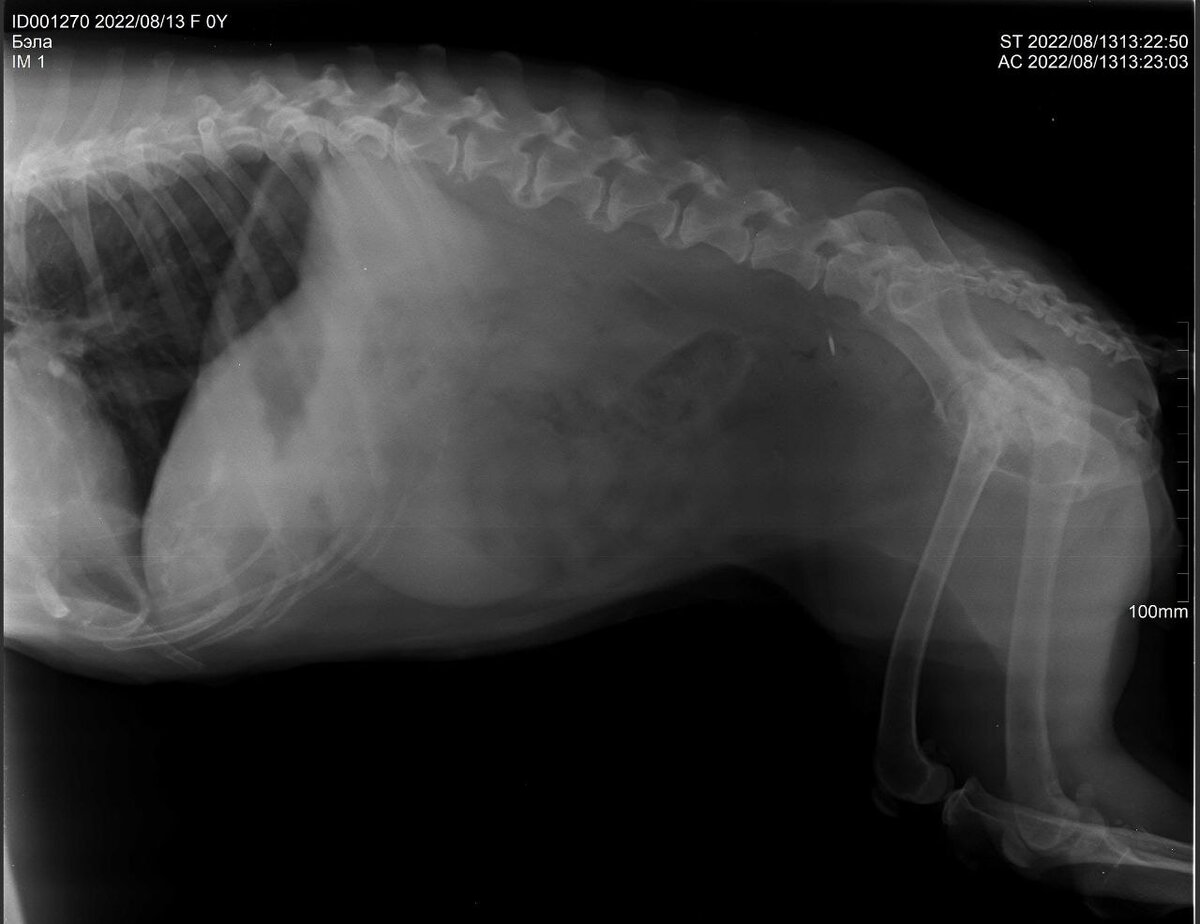

Дикушка Бэла и её проблемы с позвоночником

На днях я возил Бэлу в клинику, потому что у неё начались проблемы с задними лапами. Как выяснилось, срослись позвонки и стёрлись суставы в тазобедренном, из-за чего она стала плохо ходить и заваливаться.